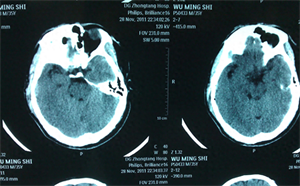

所以,一般来说,空心的啤酒瓶砸在人的头上并不会轻易碎裂,反而是人的头部被击中后,可能会因为用力过猛导致脑出血,昏迷,甚至可能引发颅骨骨折。

更严重的情况是脑震荡,脑震荡是对大脑更加深沉的伤害,可能导致人的记忆力下降,精神错乱等等可怕症状。

这是因为在强烈的力量撞击下,颅骨会发生移动,、如果里面的大脑也随之发生了位移,导致内部神经错位,就会形成脑震荡。

脑震荡的症状表现有很多,程度较轻的会出现短时间内的意识障碍,也有人在清醒之后会遗忘掉受伤时的情况以及受伤经过,其他的后遗症也有很多,比如头晕、恶心、头疼、呕吐、耳鸣、注意力不紧张和反应迟钝等,都是比较常见的一些症状。